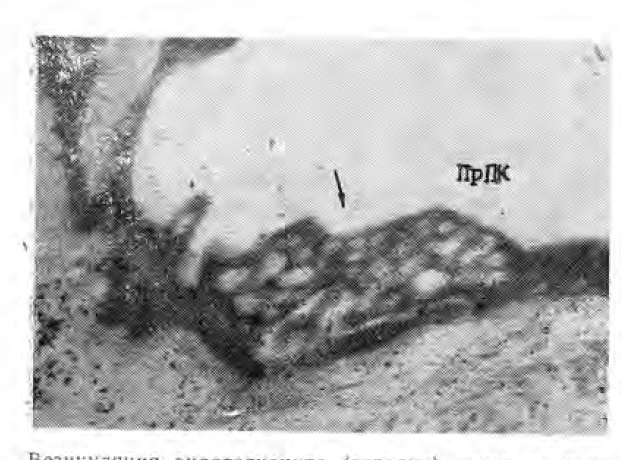

К концу 3-й недели в эндотелиальных клетках перифолликулярных капилляров обнаруживается большое количество крупных везикул, которые по мере их слияния формируют вакуоли, а затем кавеолы (крупные полости), нередко занимающие почти всю цитоплазму клетки (см. рис.).

Везикуляция эндотелиоцита (стрелка) посткапилляра -щитовидной железы кота. Срок эксперимента — 20 суток. ПрПК — просвет посткапилляра. Х26 600.